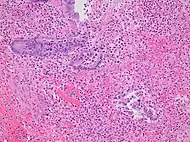

Pathology

Even for clinically certain appendicitis, routine histopathology examination of appendectomy specimens is of value for identifying unsuspected pathologies requiring further postoperative management.[61] Notably, appendix cancer is found incidentally in about 1% of appendectomy specimens.[62]

Pathology diagnosis of appendicitis can be made by detecting a neutrophilic infiltrate of the muscularis propria.

Periappendicitis (inflammation of tissues around the appendix) is often found in conjunction with other abdominal pathology.[63]

Micrograph of appendicitis and periappendicitis. H&E stain

Micrograph of appendicitis showing neutrophils in the muscularis propria. H&E stain

Acute suppurative appendicitis with perforation (at right). H&E stain